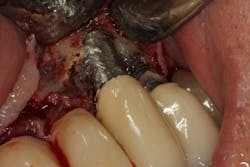

Once again, the literature is replete with case reports and case series describing soft- and hard-tissue loss due to excess dental cement left at the time of implant crown insertion.8 In one study, 90% of the implant crowns inserted with cement exhibiting inflammation and bleeding upon probing were due to cement in the peri-implant sulcus.9 Cement acts as a nidus for bacteria and induces a rapid hard-tissue loss around the dental implant fixture (figures 2 and 3).

Detecting excess cement can usually be done with a radiograph if the cement is located in the interproximal region and is radiopaque (figure 4).